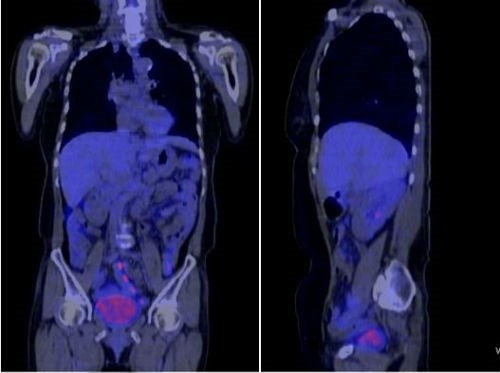

Hình ảnh phim chụp CT của bà Hà đã không còn dấu vết của ung thư. |

Bà Hà được bác sĩ tiến hành điều trị hóa trị. Sau 2 chu kỳ điều trị, sức khỏe bà Hà tiến triển tốt, không sụt cân, không còn buồn nôn. Với những bệnh nhân như bà Hà, GS Khoa cho rằng đã được xác định là thành công. Các chẩn đoán dựa trên hình ảnh đều không thấy có tổn thương vùng thận, xương chậu.